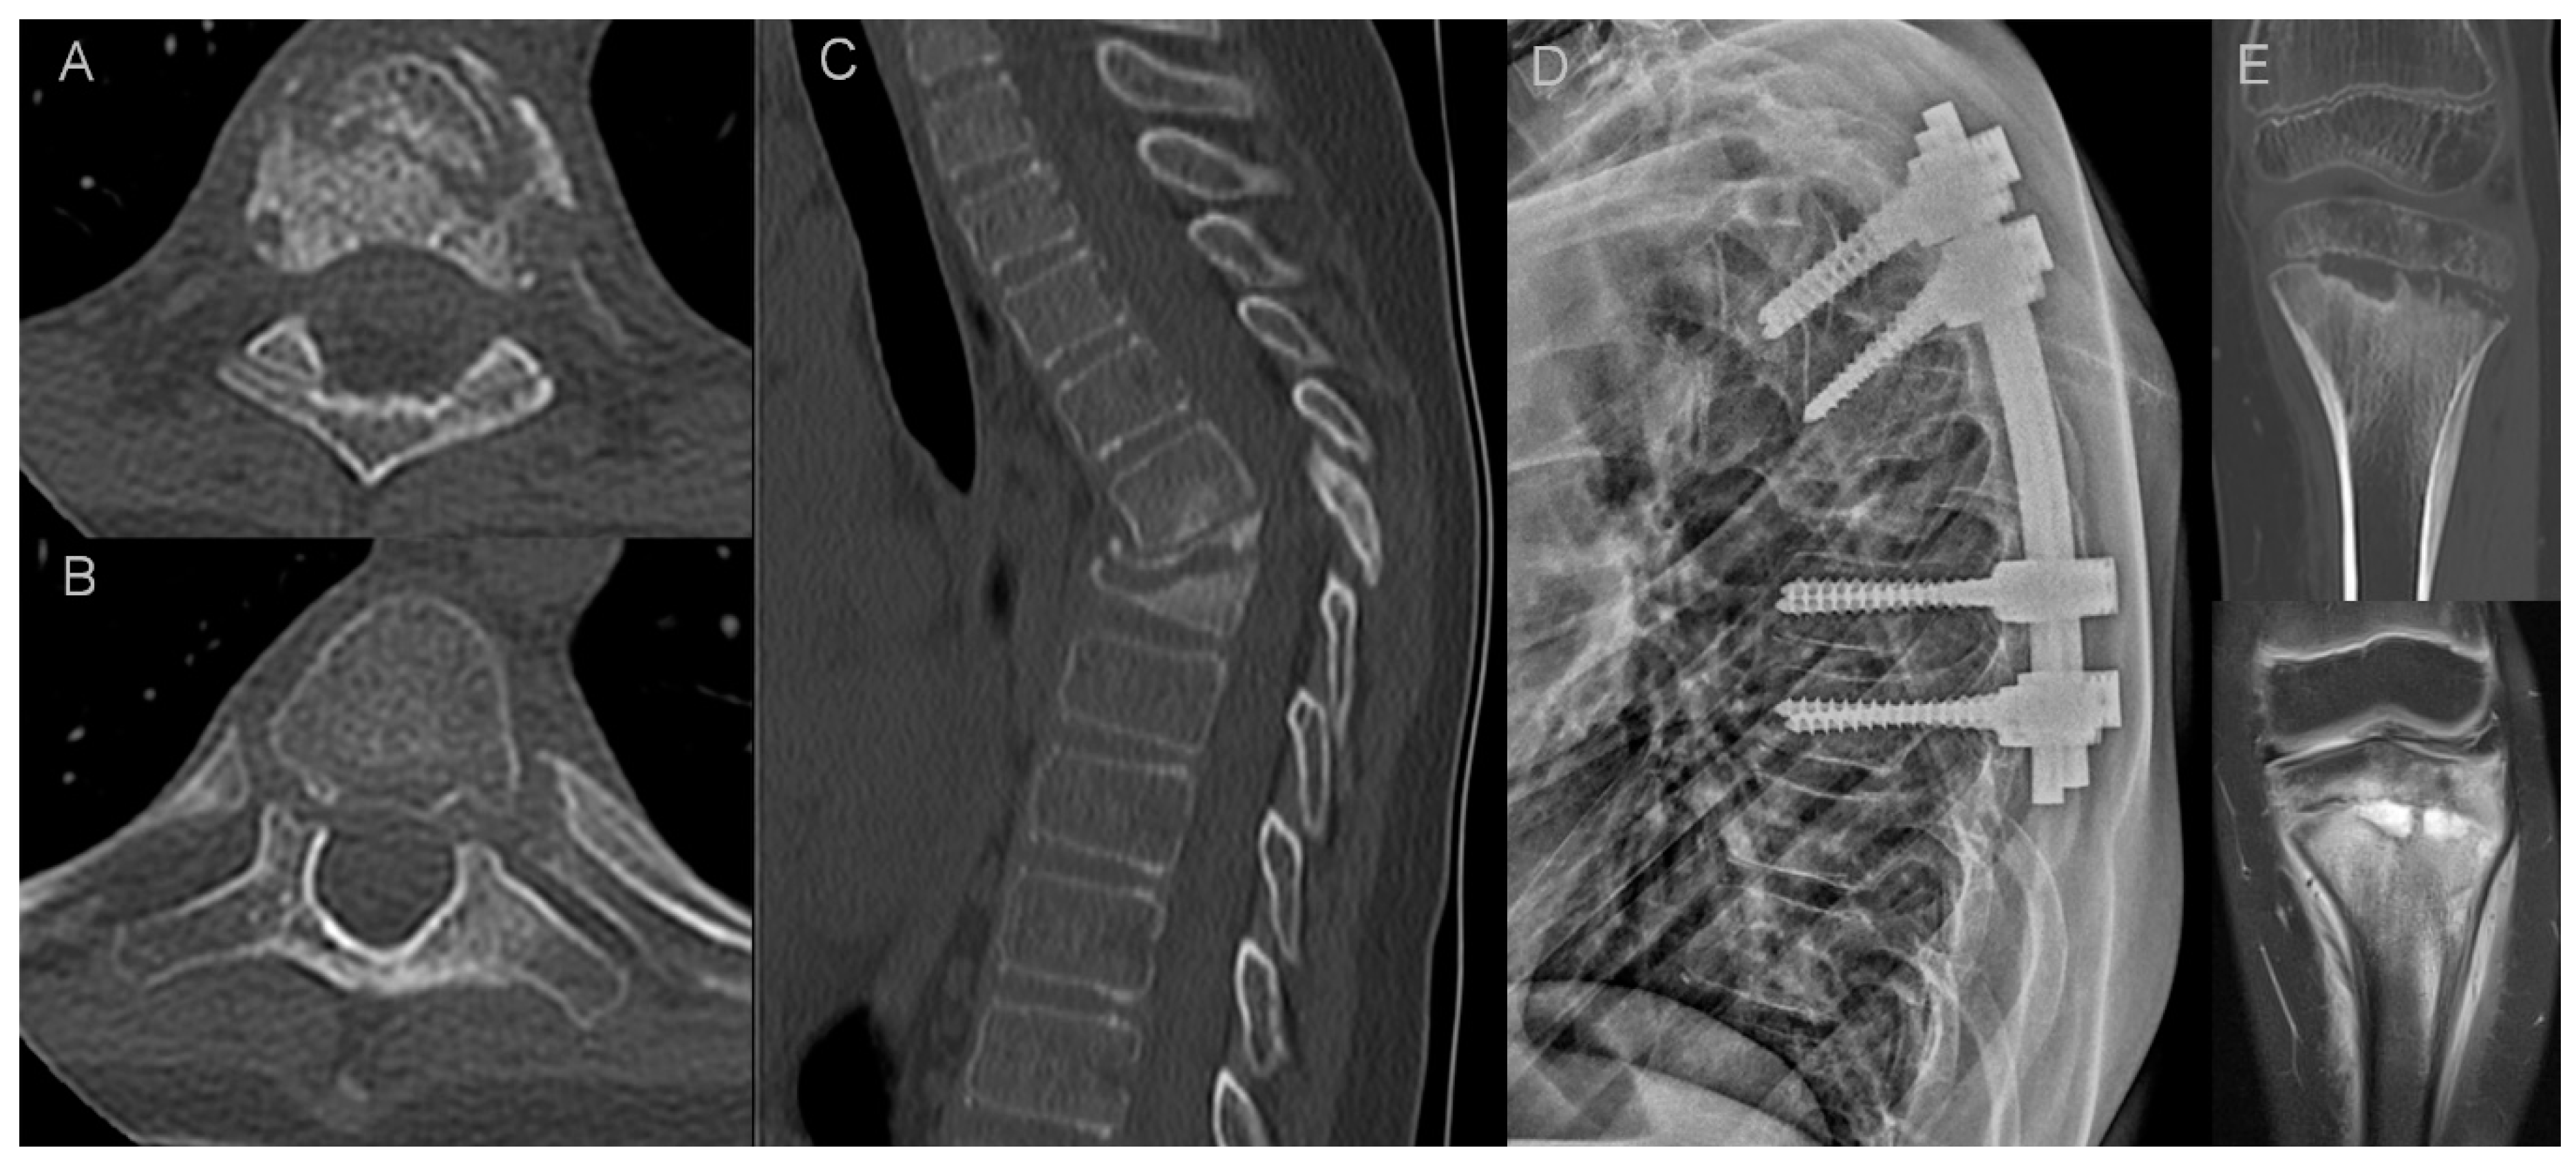

In two pediatric patients of our cohort, there was a destruction of vertebral bodies with vertebra plana deformity and progressive kyphosis that eventually required surgery (Figure 3). There are several reports on an aggressive course of CRMO in the pediatric population with a rapid destruction of vertebral bodies and vertebra plana formation in some patients, on multiple levels, as recapped in the article by Anderson and coworkers [25]. This aggressive course requires differential diagnosis with pyogenic spondylodiscitis and neoplastic disease [26]. To make things more difficult, a clinical presentation of pediatric bacterial spondylodiscitis may be similar to CRMO, since laboratory findings are often unremarkable, showing only a slight to moderate increase in inflammatory markers [27]. The hallmarks of pyogenic spondylodiscitis are disc signal changes and paraspinal soft tissue inflammation with phlegmon or abscess formation [27,28]. Those features were completely absent in both children with vertebra plana and one young adult with marginal vertebral body destructive lesions in our study group. Langerhans cell histiocytosis (LCH) is considered the most common cause of vertebra plana in children; however, a recent report has showed a higher-than-expected incidence of non-LCH diagnoses with a high rate of other malignancies and non-malignant causes, including CRMO [29,30,31]. The lack of vertebral wall bulging and paraspinal soft tissue mass may be helpful in differentiating CRMO from malignancy. However, in our opinion, the features of inflammatory arthritis of costovertebral and facet joints are the most important discriminator. Erosions in costovertebral and facet joints were present in all patients with vertebral body destruction in our study group (Figure 3). According to our experience, those subtle changes in spinal joints are easier to appreciate on CT than MRI thanks to higher resolution and multiplanar reformatting capabilities of the former. In addition, the distribution of lesions may help in differentiating CRMO from LCH, which most often presents as a monofocal osseous lesion [29,30]. Both children in our material had a concomitant long bone involvement (Figure 3).

Figure 3.

Imaging findings in a 10-year-old patient with CRMO (patient 16.). Axial CT scans show erosions in the facet (A) and costovertebral (B) joints. Sagittal CT reformat shows osteodestructive lesions with vertebra plana deformity (C) that led to progressive kyphosis with spinal stenosis requiring transpedicular stabilization (D). Another site of the disease was found in the tibia (E) with CT and MRI showing metaphyseal osteolysis with adjacent osteosclerosis, extensive bone marrow edema and solid periosteal reaction.